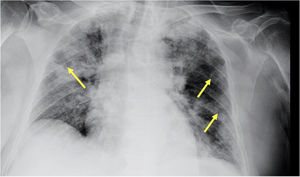

A los 6 días del inicio de la fiebre se consultó con el Servicio de Enfermedades Infecciosas por persistencia de esta, aparición de expectoración herrumbrosa y desarrollo de insuficiencia respiratoria. El paciente persistía con neutropenia severa y, pese al tratamiento antibiótico, la proteína C reactiva había aumentado a 480mg/L. Dos cultivos de esputo y varias tandas de hemocultivos habían sido negativos. Se realizó una nueva radiografía de tórax en la que se objetivaron infiltrados pulmonares periféricos bilaterales (fig. 1).